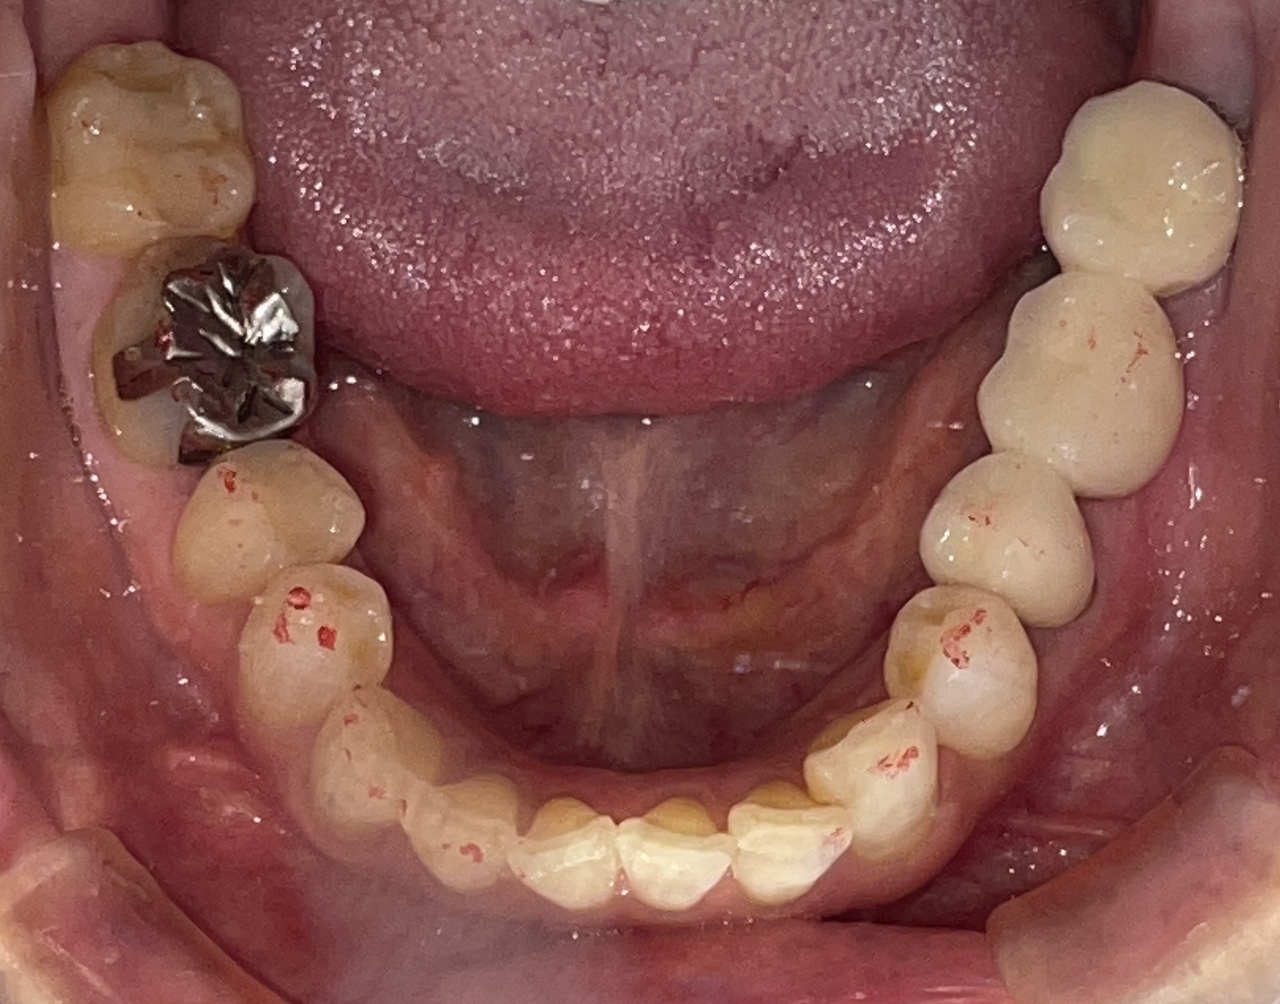

Before

After

矯正の種類 / invisalign GO

年齢・性別 / 10代女性

主訴  /  上下顎叢生

治療期間 / 13ヶ月

費用 / 簡易検査 5,000円(税別) 精密検査 30,000円(税別)

両顎マウスピース 450,000円(税別) 両顎リテイナー料 40,000円(税別)

※マウスピース交換時別途調節料5,000円(税別)

副作用 / 口内炎・歯の移動に伴う痛み・知覚過敏 ※数日で収まる場合が多いです

リスク / 後戻り防止の為、夜のみマウスピースで保定を指示